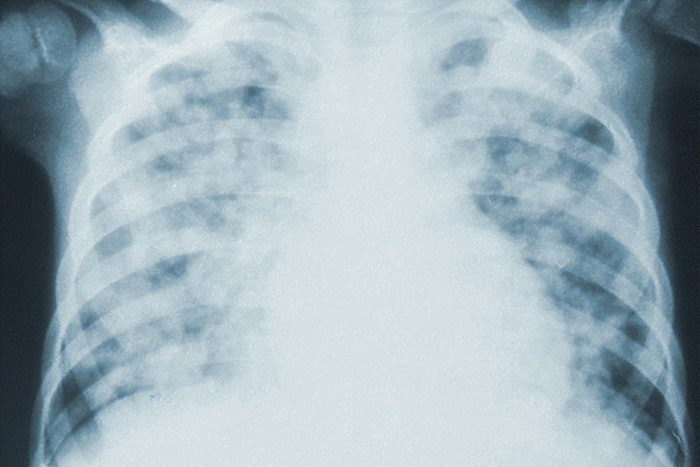

В Петербурге 600 больных коронавирусом находятся в реанимации, из них 300 подключены к аппаратам ИВЛ. Об этом сообщил председатель комитета по здравоохранению Дмитрий Лисовец в эфире телеканала «Санкт-Петербург».

Лисовец говорит, что в течение последних двух недель количество пациентов, подключенных к ИВЛ, и пациентов в реанимации остается стабильным. Коечного фонда в городе, по его словам, хватает. До 80 % зараженных коронавирусом болеют в легкой форме, заявил глава комздрава.